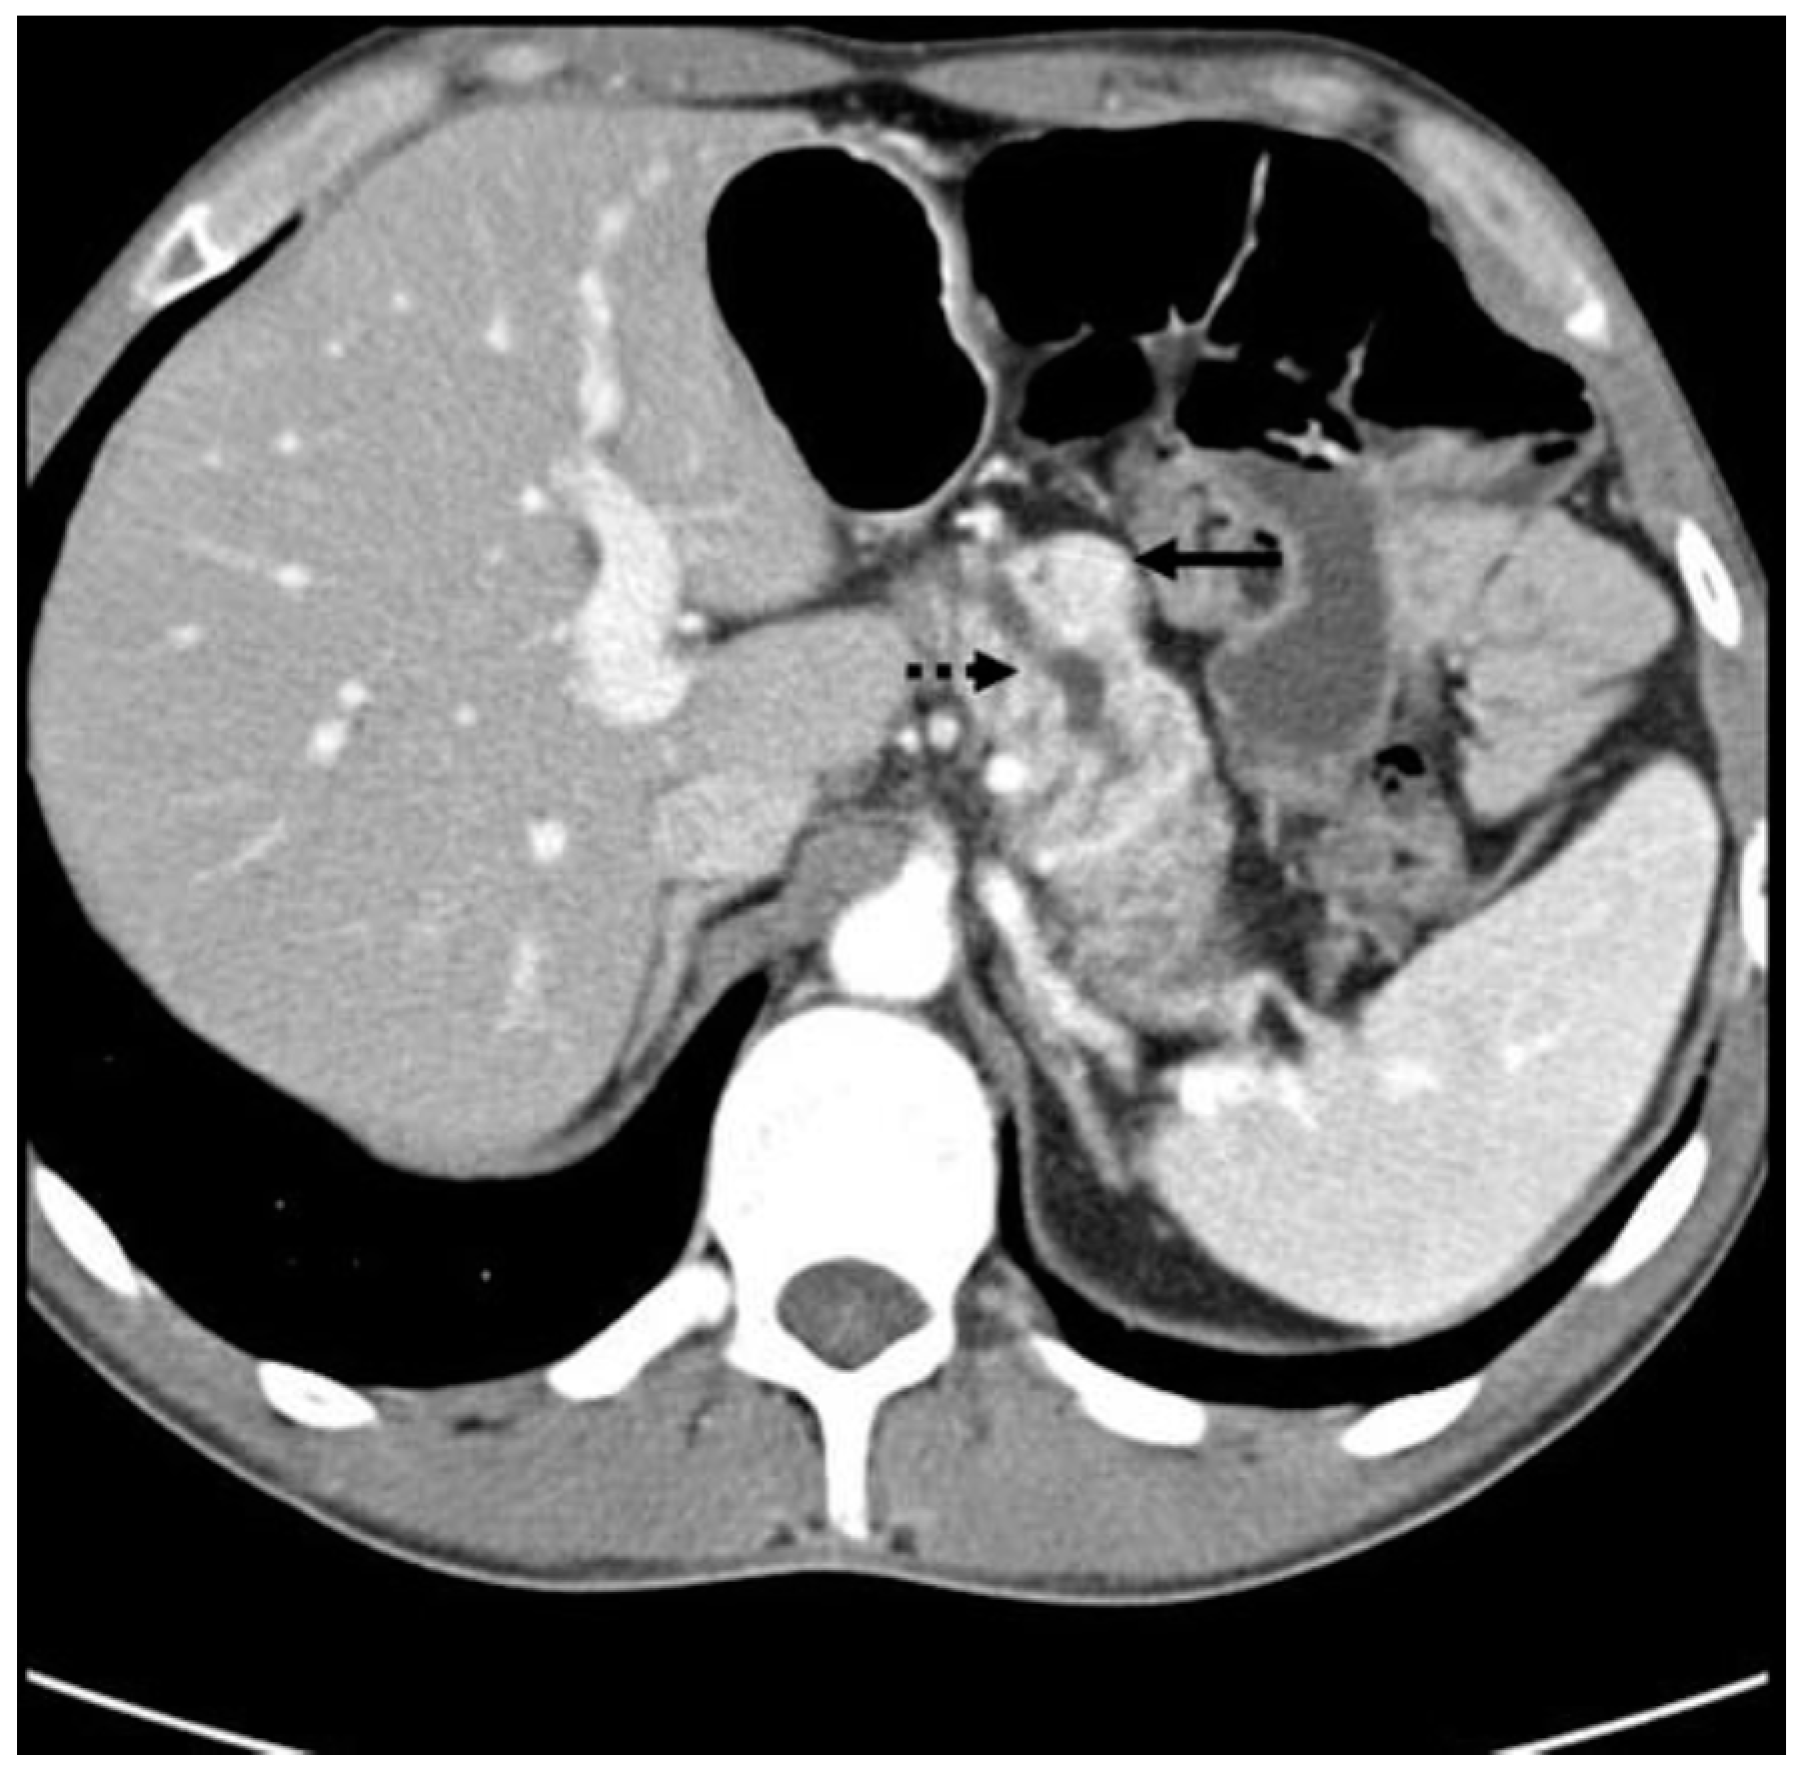

Figure 6.

CT scan showing a PPoma of the head (solid arrow) of the pancreas causing pancreatic duct dilation (dashed arrow). The tumor is a discrete lesion, with well-defined borders, and shows contrast enhancement in the arterial phase [].